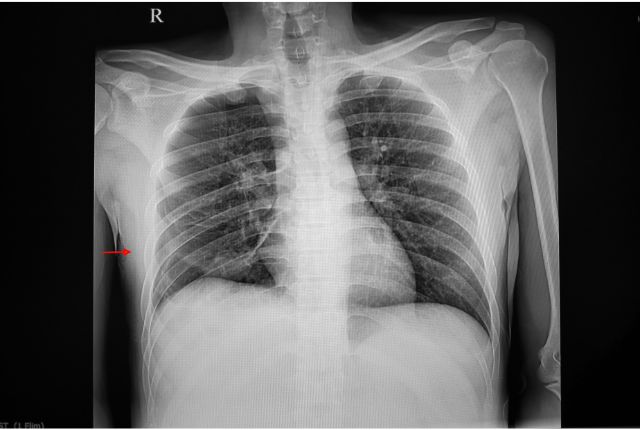

- Le diagnostic peut être confirmé grâce à la radio qui permet aussi de voir l’étendue du problème ;